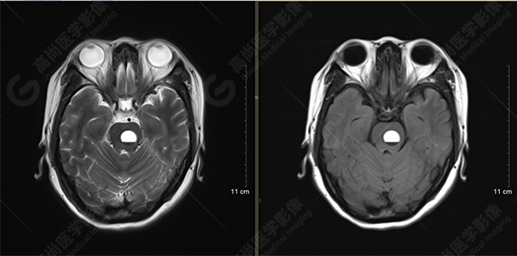

T2WI及FLAIR序列

影像表現(xiàn):橋腦見一類圓形異常信號影,直徑約1.3cm,呈T1WI稍高信號,T2WI及FLAIR序列高信號,其內(nèi)見高低信號分層,增強后無明顯強化。大腦鐮前部旁見兩個結(jié)節(jié)影,較大者直徑約1.4cm,呈各序列等信號,增強后呈均勻明顯強化,鄰近大腦鐮增厚、強化。右側(cè)額葉腦白質(zhì)內(nèi)見一斑點狀等T1長T2信號影,F(xiàn)LAIR序列呈高信號,增強后無強化;余腦實質(zhì)內(nèi)未見局灶性信號異常,增強后未見異常強化。各腦室、腦池大小、形態(tài)均正常,中線結(jié)構(gòu)居中,幕下小腦無異常。矢狀面示垂體大小形態(tài)正常,未見局灶性信號異常。